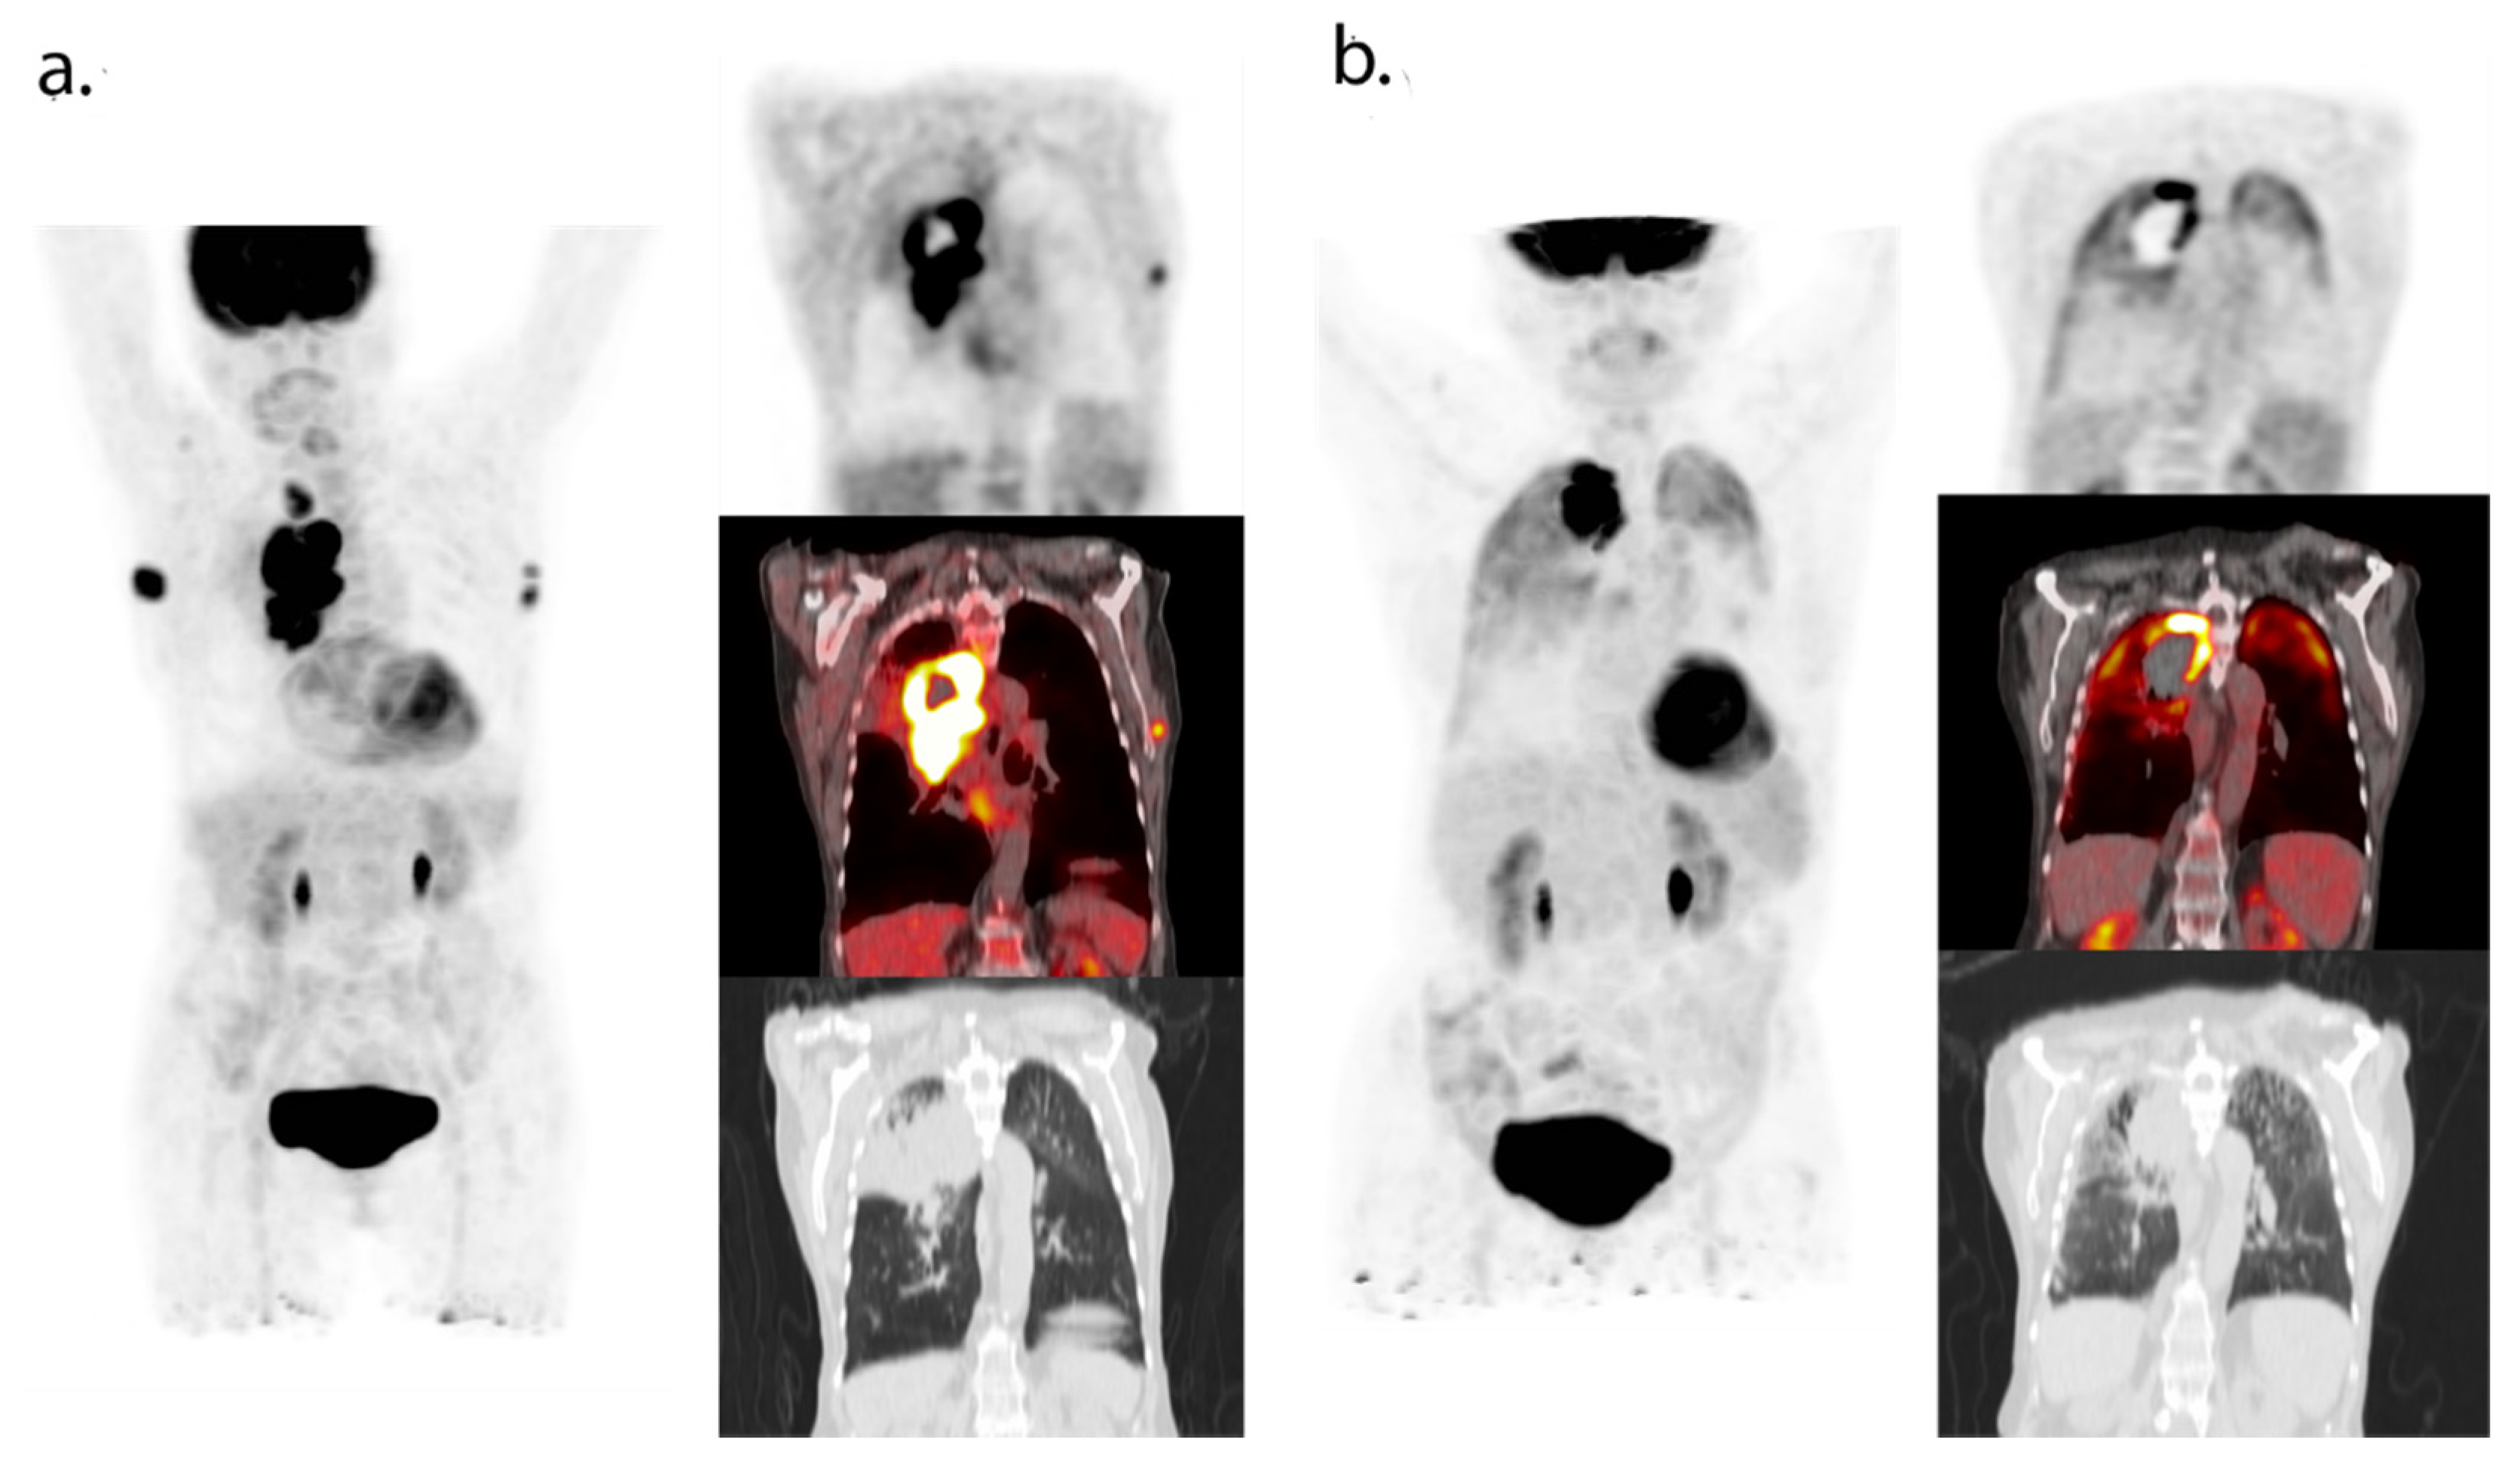

- Humbert, O.; Cadour, N.; Paquet, M.; Schiappa, R.; Poudenx, M.; Chardin, D.; Borchiellini, D.; Benisvy, D.; Ouvrier, M.J.; Zwarthoed, C.; et al. 18FDG PET/CT in the early assessment of non-small cell lung cancer response to immunotherapy: Frequency and clinical significance of atypical evolutive patterns. Eur. J. Nucl. Med. Mol. Imaging 2019, 47, 1158–1167. [Google Scholar] [CrossRef]

- Castello, A.; Rossi, S.; Toschi, L.; Lopci, E. Comparison of metabolic and morphological response criteria for early prediction of response and survival in nsclc patients treated with anti-PD-1/PD-L1. Front. Oncol. 2020, 10, 1090. [Google Scholar] [CrossRef] [PubMed]

- Tan, A.C.; Emmett, L.; Lo, S.; Liu, V.; Kapoor, R.; Carlino, M.S.; Guminski, A.D.; Long, G.V.; Menzies, A.M. FDG-PET response and outcome from anti-PD-1 therapy in metastatic melanoma. Ann. Oncol. 2018, 29, 2115–2120. [Google Scholar] [CrossRef]

- Kong, B.Y.; Menzies, A.M.; Saunders, C.A.B.; Liniker, E.; Ramanujam, S.; Guminski, A.; Kefford, R.; Long, G.V.; Carlino, M.S. Residual FDG-PET metabolic activity in metastatic melanoma patients with prolonged response to anti-PD-1 therapy. Pigment. Cell Melanoma Res. 2016, 29, 572–577. [Google Scholar] [CrossRef]